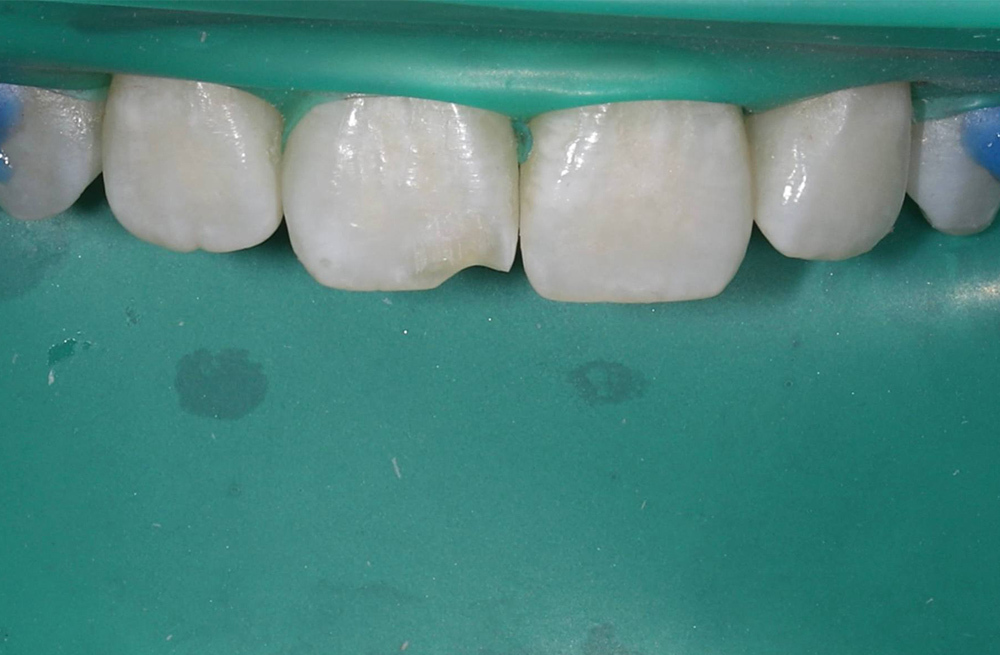

Восстановление сколотого края центрального резца композитомпри травматическом переломе коронки

Восстановление отколотого переднего зуба у подростка за один визит

Восстановление скола переднего зуба после травмы у подростка